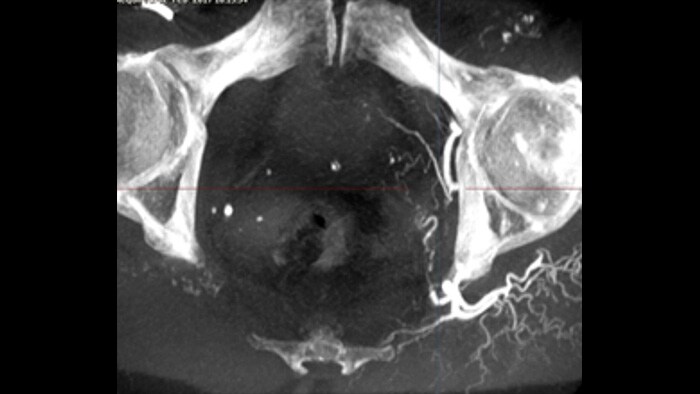

XperGuide offers live 3D image needle guidance, letting you bring percutaneous needle procedures into the Hybrid OR. It overlays live fluoroscopy and 3D soft tissue imaging data from previously acquired CT or MR scans or Philips XperCT, providing information on the needle path and target.